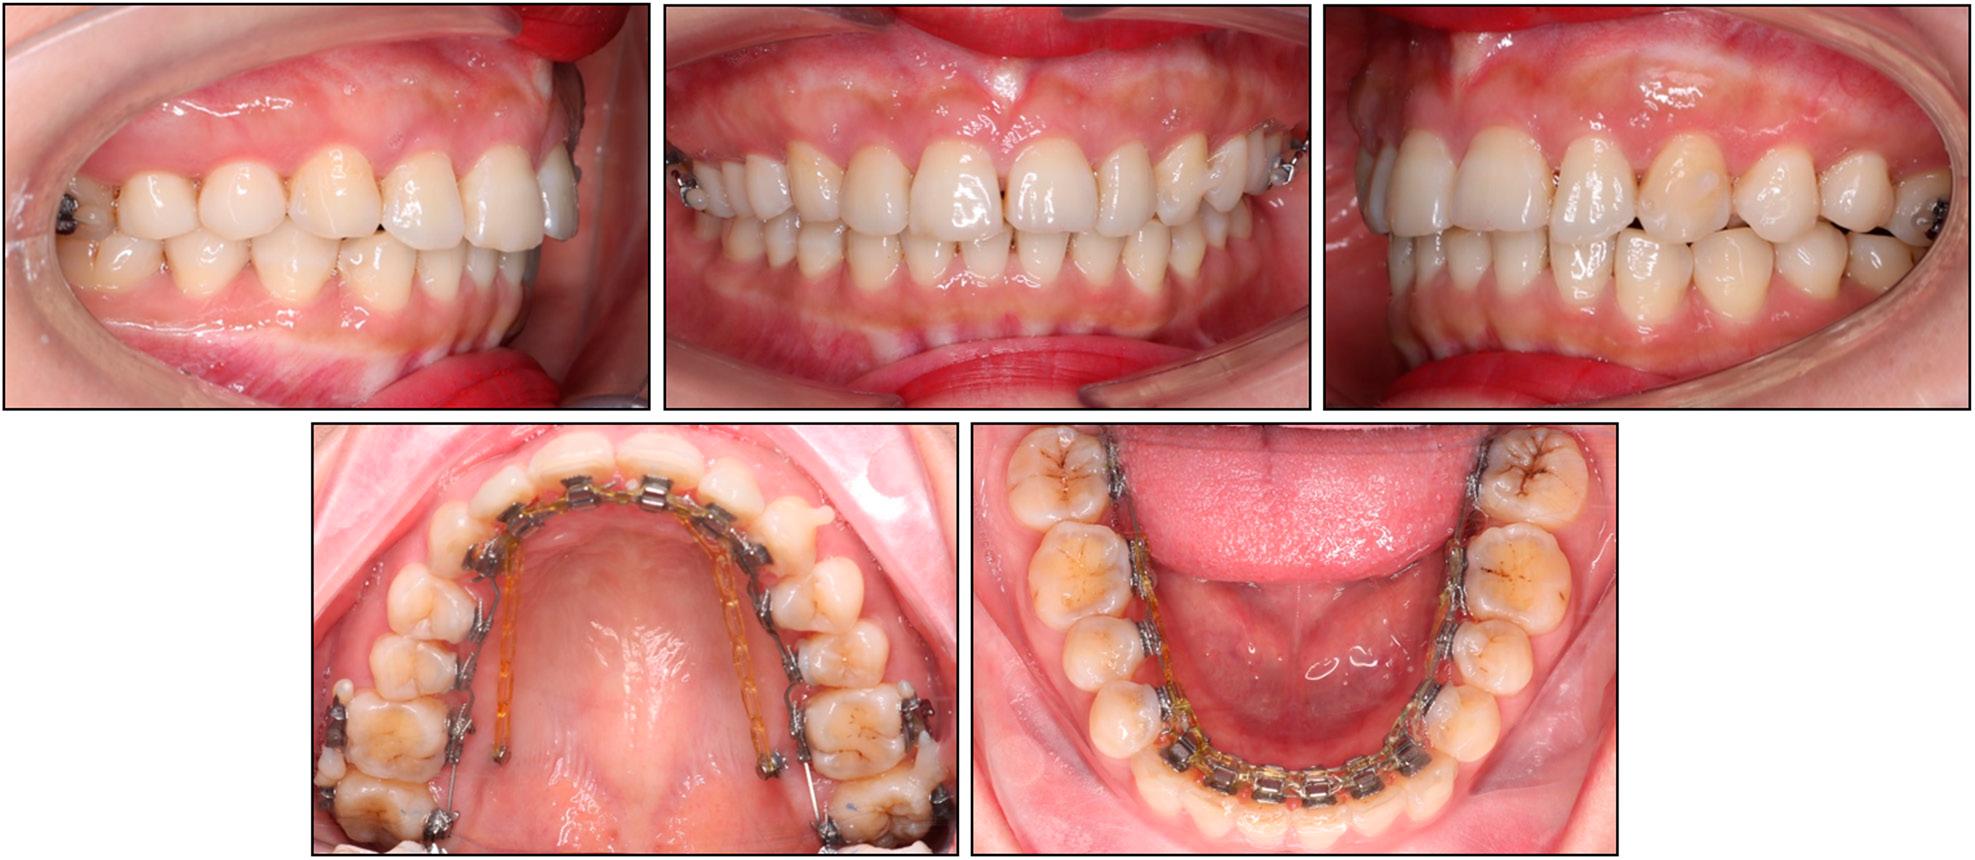

The lateral cephalometric analysis revealed a skeletal Class II relationship with a normally positioned mandible and a protruded maxilla (SNA: 85.7°, SNB: 79.6°, ANB: 6.1°). The vertical skeletal pattern was hypodivergent (FMA: 20.0°). The upper incisors were severely retroclined (U1/SN: 80.3°) while the lower incisors were slightly proclined (IMPA: 94.2°). The upper incisal display was large (5.8 mm). The upper and lower lips were normally placed (upper lip to E-line, -0.7 mm; lower lip to E-line, -1.2 mm) (Table I). The panoramic radiograph showed the presence of all teeth except the mandibular right third molar (Figure 2).

Case 1: initial panoramic and cephalometric radiographs and tracing.

The cephalometric analysis showed a skeletal Class II relationship with a slightly retruded mandible and a protruded maxilla (SNA: 85.5°, SNB: 75.8°, ANB: 9.7°). The vertical skeletal pattern indicated a slight hypodivergence (FMA: 21.4°). The upper incisors were excessively retroclined (U1/SN: 73.9°) while the lower incisors were proclined (IMPA: 103.4°). The upper incisal display was slightly increased (3.7 mm). The upper lip was slightly protruded but the lower lip was normally placed (upper lip to E-line, 1.9 mm; lower lip to E-line, 0.2 mm) (Table II). The panoramic radiograph indicated the presence of all teeth, excluding the mandibular left third molar (Figure 10).

Case 2: initial panoramic and cephalometric radiographs and tracing.